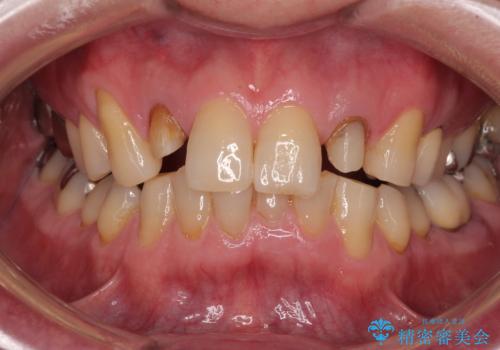

- 前歯の色味が気になるとのことで来院された患者様です。左上の2番目の歯の歯茎のラインと被せものの境目の適合が悪い状態だったのでオールセラミッククラウンによる補綴治療を行っていくことになりました。

金属の土台を外し、ファイバーコアを築造し、オールセラミッククラウンに適切な形に整えました。

左上の2番目の歯の型どりの段階で患者様より右上の2番目の歯も治療をしてほしいとのことで、根管治療(保険診療)、ファイバーコア、オールセラミッククラウンによる補綴治療を行いました。